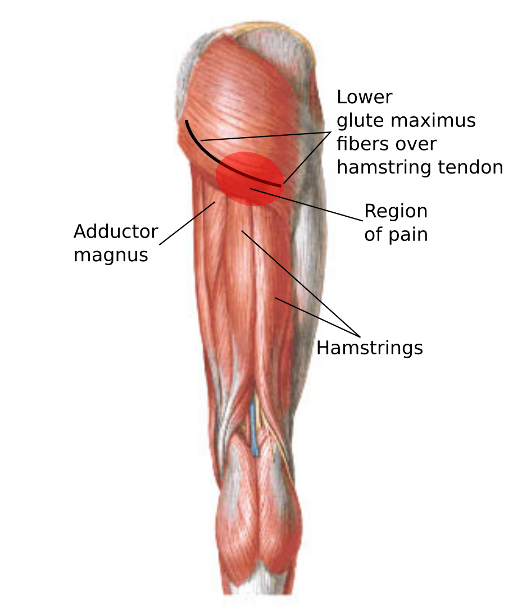

Анатомия и Функции Мышцы Adductor Magnus